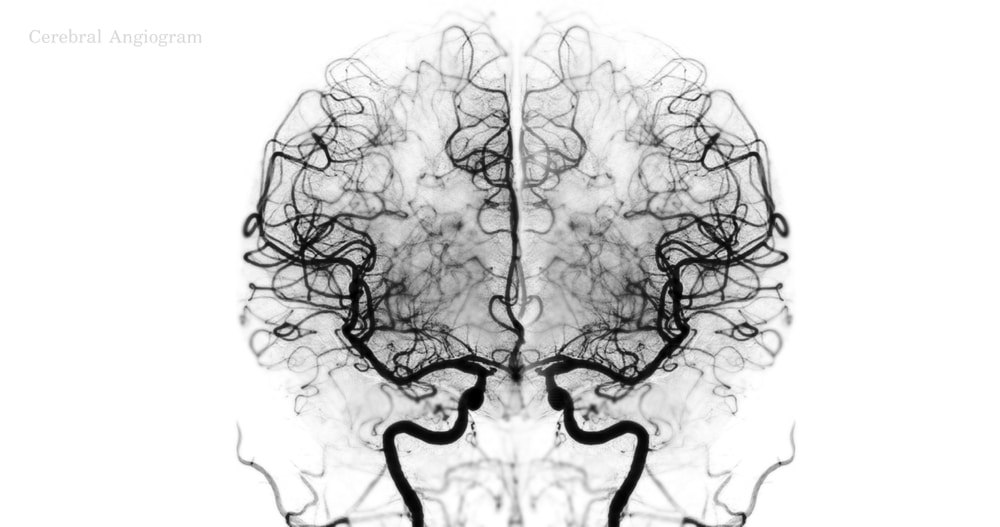

- Aerobic exercises benefit gray matter (wealthy in the central nervous system), the hippocampus, and memory

- Resistance training has a pronounced influence on white matter—the brain’s fast-connection pathways crucial for decision-making and executive function

This distinction holds significant weight: “The structure and function of white matter are among the strongest indicators of cognitive decline and risk for dementia,” Wood asserts. “Resistance training appears to uniquely bolster both the structure and function of white matter.”

White matter plays a crucial role in swift decision-making, impulse control, and maintaining sharpness during high-pressure situations. Therefore, for those regularly lifting weights, you’re reaping benefits for both your physical health and brain well-being.